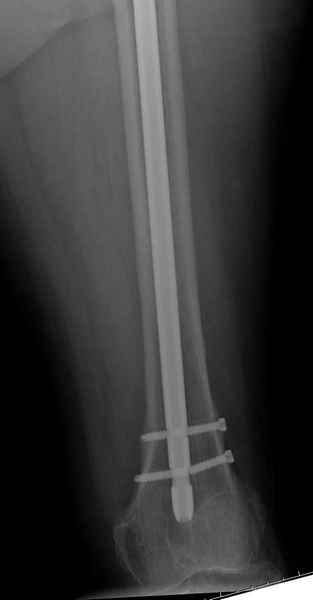

77 летняя больная направлена в нашу клинику на дальнейшее лечение. Из истории, травму получила в сентябре 2007 года и по поводу перелома шейки бедра больная была проперирована тремя каннюлированными шурупами с явным нарушением технологии установки шурупов. Внизу вместо одного шурупа имеется два, что привело к стрессу латерального кортекса. Через месяц по поводу ятрогенного подвертельного перелома сделана фиксация длинной Гамма 3. Установлен без проксимальной блокировки? (set screw). В данный момент имеется несостоятельность конструкции и ложный сустав. Передвигается с помошью костылей, конечность укорочена на 2 см. Какие будут рекомендации?Djoldas Kuldjanov, MDDepartment of Orthopedic SurgerySt. Louis University Medical Center

Я не вижу на снимках нестабильности конструкции (разве что гнутый дистальный винт).

Михаил, здравствуйте. Если присмотреться - на четвертом снимке есть перелом гвоздя по отверстию.

Видимо, проблем тут две: во-1-х, центральный отломок был оставлен в варусно-сгибательной установке, во-2-х, не динамизировали вовремя.

Нижние винты хотели сломаться, но, увы, один не сломался, и тогда сломался гвоздь. Хотя и при динамизации в таком положении отломков

могло не срастись.